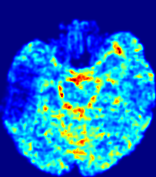

LesionRefer to captionRefer to captionRefer to captionRefer to captionRefer to captionRefer to caption𝐕rgbsubscript𝐕𝑟𝑔𝑏{\bf{V}}_{rgb}Refer to captionRefer to captionRefer to captionRefer to captionRefer to captionRefer to caption𝐕2subscriptnorm𝐕2{\|\bf{V}}\|_{2}Refer to captionRefer to captionRefer to captionRefer to captionRefer to captionRefer to captionRefer to caption3.53.53.52.82.82.82.12.12.11.41.41.40.70.70.70.00.00.0(mm/s)𝑚𝑚𝑠(mm/s)D𝐷DRefer to captionRefer to captionRefer to captionRefer to captionRefer to captionRefer to captionRefer to caption0.0200.0200.0200.0160.0160.0160.0120.0120.0120.0080.0080.0080.0040.0040.0040.0000.0000.000(mm2/s)𝑚superscript𝑚2𝑠(mm^{2}/s)Slice #1Slice #2Slice #3Slice #4Slice #5Slice #6

Figure 4: PIANO feature maps for another patient in the ISLES 2017 training set, where the lesion is located in the right hemisphere. Top row: segmented stroke lesion region (white) on different slices. The corresponding slices for the PIANO feature maps are shown in the following rows.

For a better insight into an estimated velocity field 𝐕𝐕{\bf{V}} and diffusion field 𝐃𝐃{\bf{D}}, we compute the following maps: (1) 𝐕rgbsubscript𝐕𝑟𝑔𝑏{\bf{V}}_{rgb}: Color-coded orientation map of 𝐕=(Vx,Vy,Vz)T𝐕superscriptsuperscript𝑉𝑥superscript𝑉𝑦superscript𝑉𝑧𝑇{\bf{V}}=(V^{x},V^{y},V^{z})^{T}, obtained by normalizing 𝐕𝐕{\bf{V}} to unit length and mapping its 3 components to red, green, blue respectively; (2) 𝐕2subscriptnorm𝐕2\|{\bf{V}}\|_{2}: 222 norm of 𝐕𝐕{\bf{V}}; (3) D𝐷D: scalar field in Eq. 5.

Fig. 3 and Fig. 4 show the PIANO feature maps estimated from two ISLES 2017 patients: all are highly consistent with the lesion in both cases. Details of the blood flow trajectories are revealed in 𝐕rgbsubscript𝐕𝑟𝑔𝑏{\bf{V}}_{rgb} by the ridged patterns and the sharp changes of colors in the unaffected (right) hemisphere, while the flat patterns appearing within the lesion provide little directional information about the velocity and indicate low velocity magnitudes. Velocity magnitudes are more directly visualized via 𝐕2subscriptnorm𝐕2\|{\bf{V}}\|_{2}, from which one can easily locate the lesion where 𝐕2subscriptnorm𝐕2\|{\bf{V}}\|_{2} is low. D𝐷D also indicates lower diffusion values in the lesion, though with less contrast potentially due to the fact that it captures the accumulated effect of CA diffusion at the voxel-level.